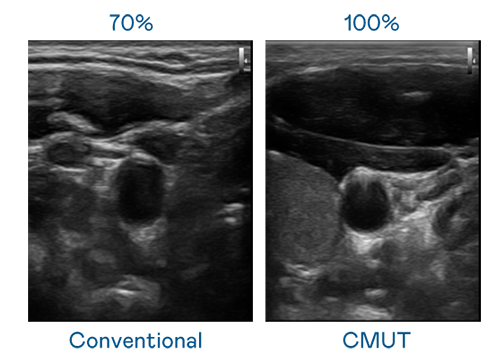

CMUT 技术是一种用电容式微机电元件来产生超音波讯号的技术。与传统 PZT 压电式技术相比,CMUT 频宽增加 30%,更宽频的超音波讯号让影像解析度大幅提升,是实现高影像品质医疗超音波扫描、促进精准医疗发展的关键技术。

大频宽带来超清晰影像

超音波影像的解析度高低,首先取决于探头能发出的讯号频宽。彩神Vll官网 CMUT 可提供高清晰的超音波讯号,提供高频宽、高灵敏度、影像纹理细节更高的超音波影像,协助医护人员缩短影像判读时间及利用精准的医疗影像进行诊断。